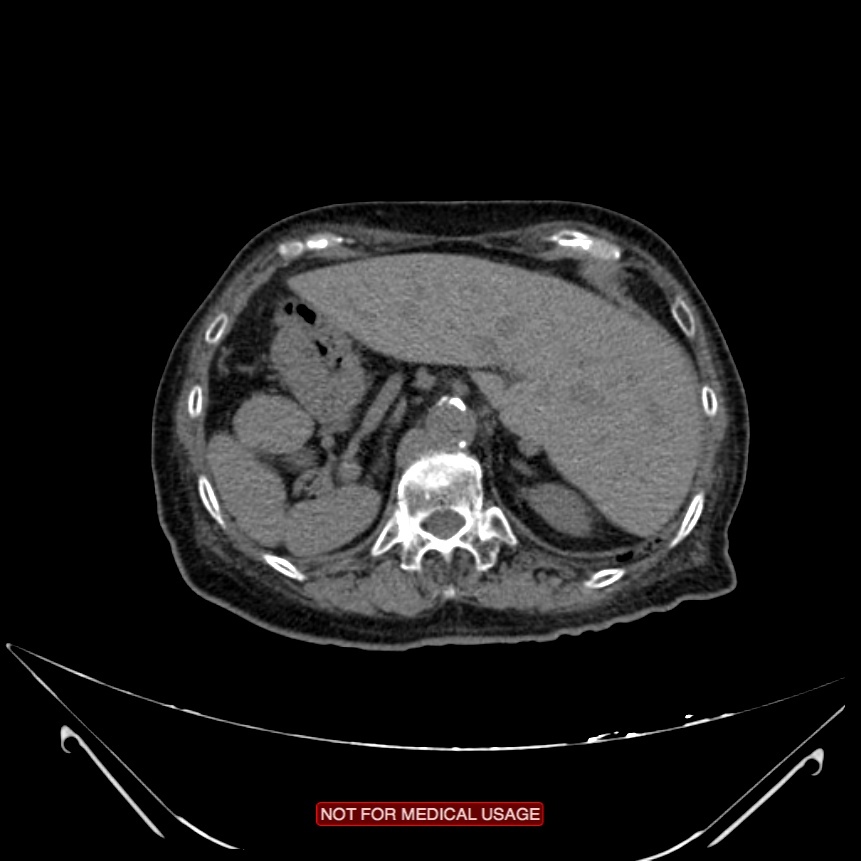

There is inversion of some abdominal structures (liver, spleen and stomach) with thoracic structures in normal position. Multiple splenules are seen on right hypochondrium. The study protocol was made for chest CT.

Case Discussion

Situs inversus partialis refers to any kind of incomplete organs inversion, like in this case. Malformations associations are more frequent in situs inversus partialis than in situs inversus totalis.

Polysplenia refers to multiple small accessory spleens.